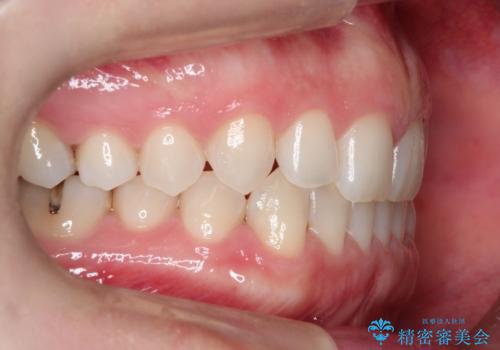

- 前歯の正中離開(すきっ歯)の改善を希望され来院された患者様です。

初診時の歯並びの状態としては、上顎中切歯間に1mm程の隙間があり、その他に見た目に関して気になるような問題点はない状態でした。

インビザライン(マウスピース)にて上顎のみの矯正治療を行いました。

見た目、嚙み合わせ及び、治療期間や施術内容に大変ご満足いただきました。